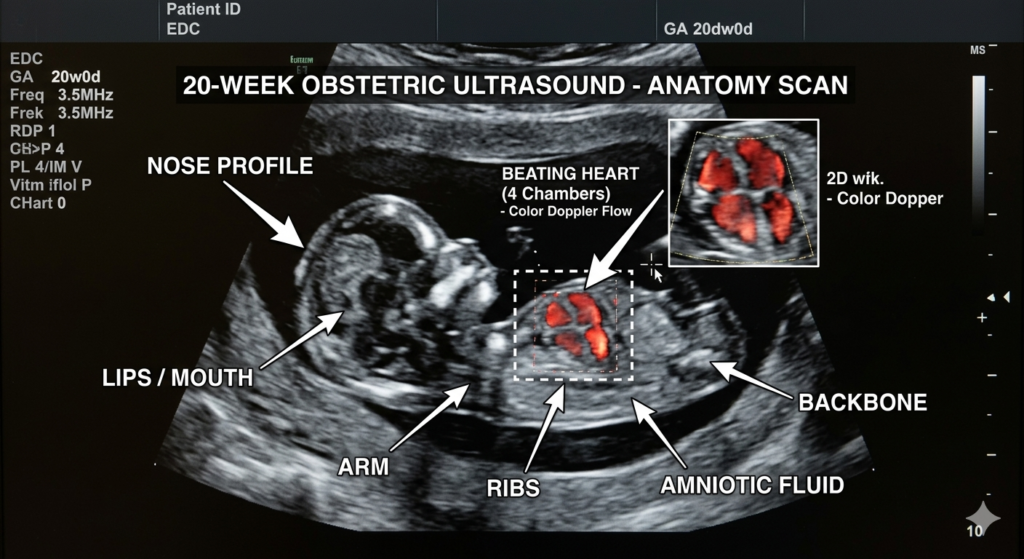

For many, the 20 weeks pregnant ultrasound (the “Anatomy Scan”) is the highlight of the second trimester. This is a 30-to-60-minute head-to-toe examination.

What the Doctor is Looking For:

- The Heart: Checking all four chambers and the major arteries.

- The Brain: Ensuring the symmetry of the cerebral hemispheres.

- The Spine: Looking for proper alignment of every vertebra.

- Placenta Position: Ensuring the placenta isn’t blocking the cervix (a condition known as placenta previa).

Real Mom Experience: “During my 20 weeks pregnant ultrasound, my baby was being so shy! I had to drink a cold glass of orange juice and walk around for 10 minutes to get them to flip over so the technician could count all ten toes. Seeing that tiny spine for the first time made everything feel so real.” — Jessica, 20 weeks.